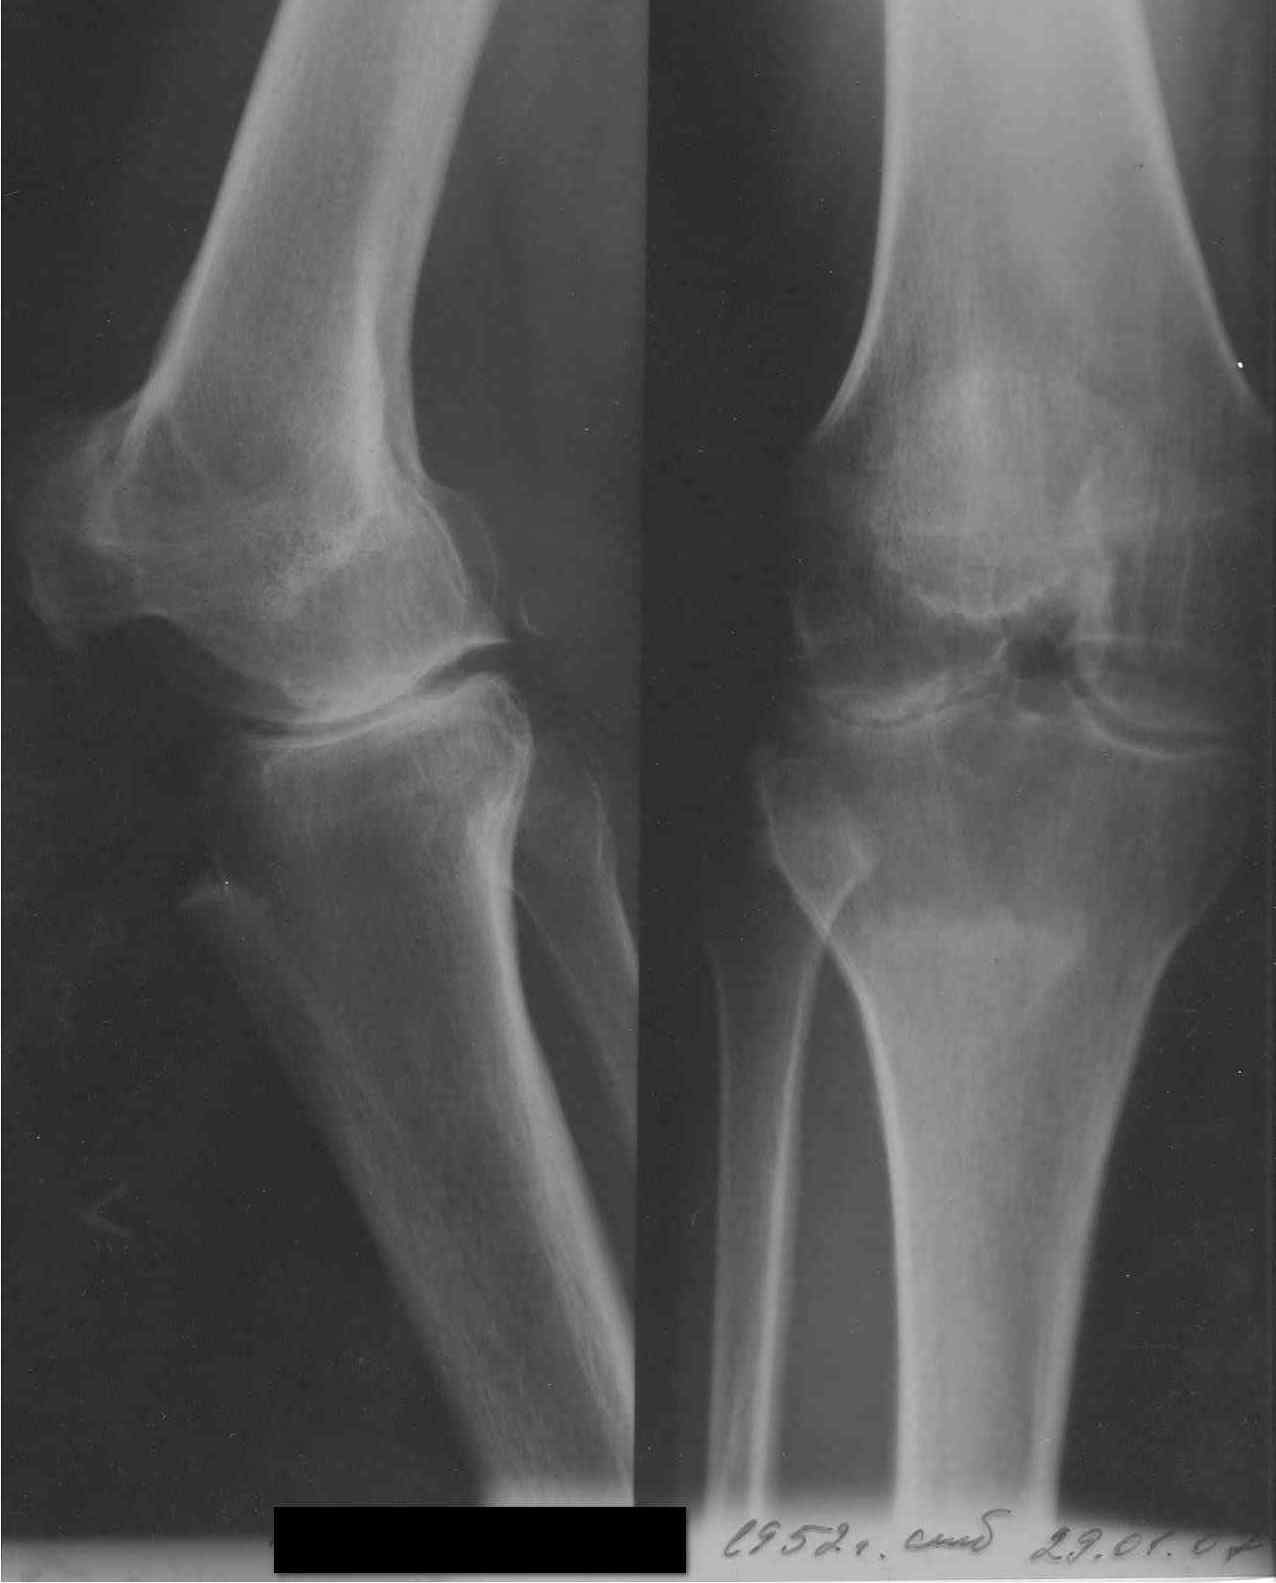

Коллеги, занимающиеся TKR, прошу совет. Обратилась пациентка 55 лет без сопутствующих проблем со здоровьем для установки коленного сустава по линии ФСС (показания установлены комиссией год назад). В программе эндопротез Зиммер LPS Legacy. После осмотра пациентки возникли сомнения в целесообразности артропластики. История: в 1998 году после серии кеналогов перенесла септический гнойный гонит с исходом в фиброзный анкилоз коленного сустава в позиции сгибания 40 град и костный анкилоз надколенниково бедренного сустава. В 1999 году в ЦИТО рекомендовано эндопротезирование (в тот период еще были движения). С 2000 года подвижности нет. Соответствующая гипотрофия 4-гл. мышцы бедра, относительное укорочение и т.д.

Вопросы: 1. Целесообразно ли эндопротезирование вообще? 2. Реально ли использование вышеуказанной модели эндопротеза в данной ситуации или следует установить "Хинч"? 3. Чем бы Вы помогли пациентке, если не надо протезировать (коррегирующий артродез приходит на ум)? Социально - инвалид 3 группы, пенсионер по возрасту, не очень богата. Спасибо заранее. Доктор А Рыков. Хабаровск. Снимки в прищепке.